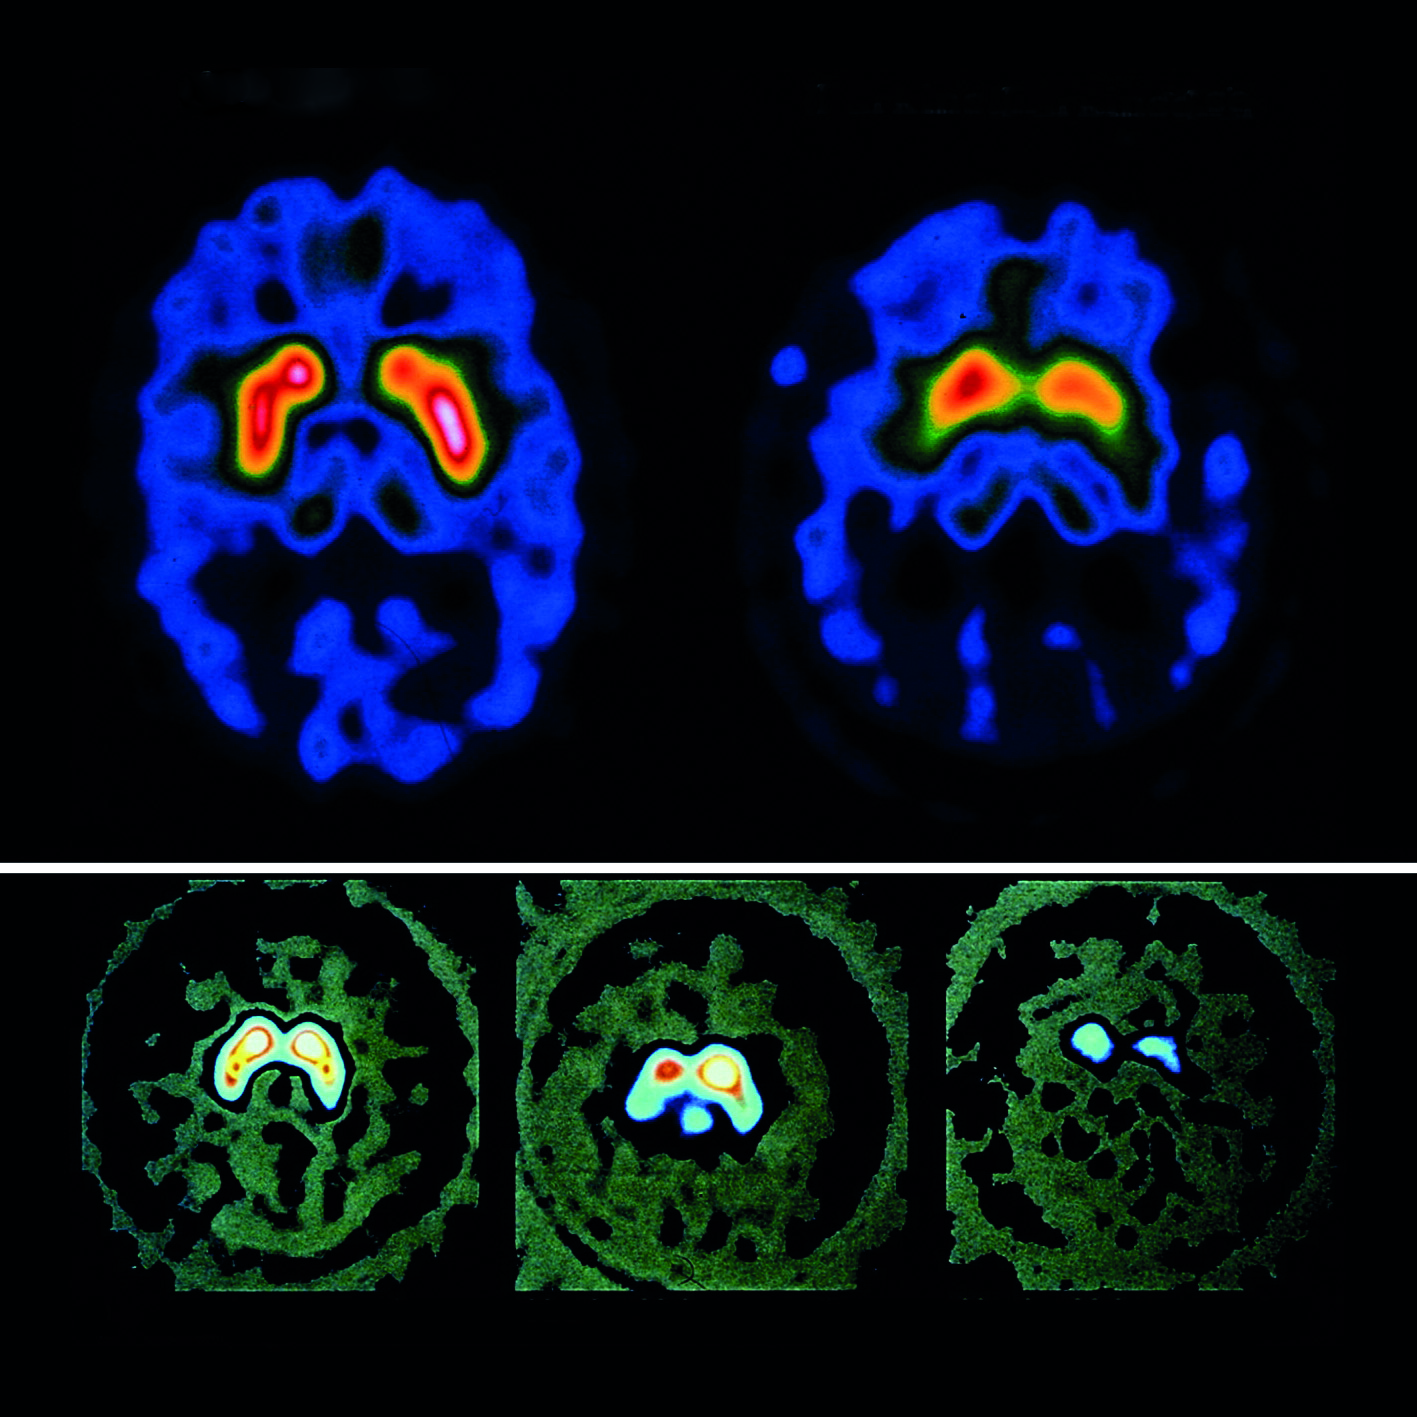

hersenscan